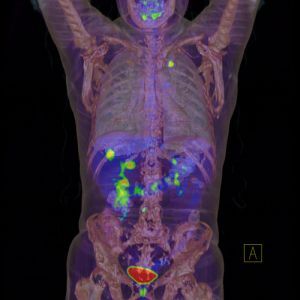

Examinarea PET/CT - O noua speranta in investigatia bolilor oncologice